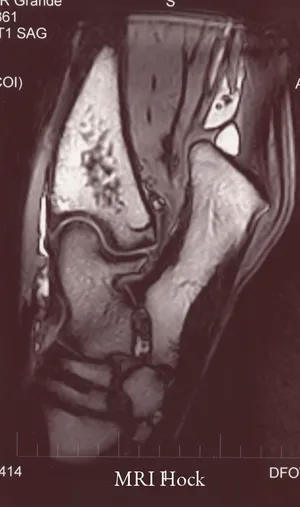

- Advanced Diagnostics & Imaging: Advanced Diagnostics, Diagnostic Imaging, Digital Radiography, Digital Radiology, Ultrasound, MRI (Magnetic Resonance Imaging), Nuclear Scintigraphy (Bone Scan), Endoscopy, and Laboratory Testing.

- State-of-the-Art Imaging: The facility is equipped with advanced diagnostic tools, including Digital Radiography, high-field MRI, and Nuclear Scintigraphy. This allows for unparalleled detail in diagnosing subtle or complicated conditions like challenging lameness issues or internal medical problems.

Choosing Equine Services, PSC is a choice for peace of mind, knowing your horse is receiving some of the best care available in Kentucky. Horse owners value the combination of world-class expertise and local convenience that this facility provides. As a full-service equine hospital, they eliminate the need for owners to seek advanced diagnostics or surgical treatment elsewhere, saving valuable time during emergencies or complex cases. The ability to perform advanced procedures, from sophisticated Lameness Evaluation using Digital Radiography and MRI to complex Orthopedic Procedures, all under one roof, is a significant advantage.